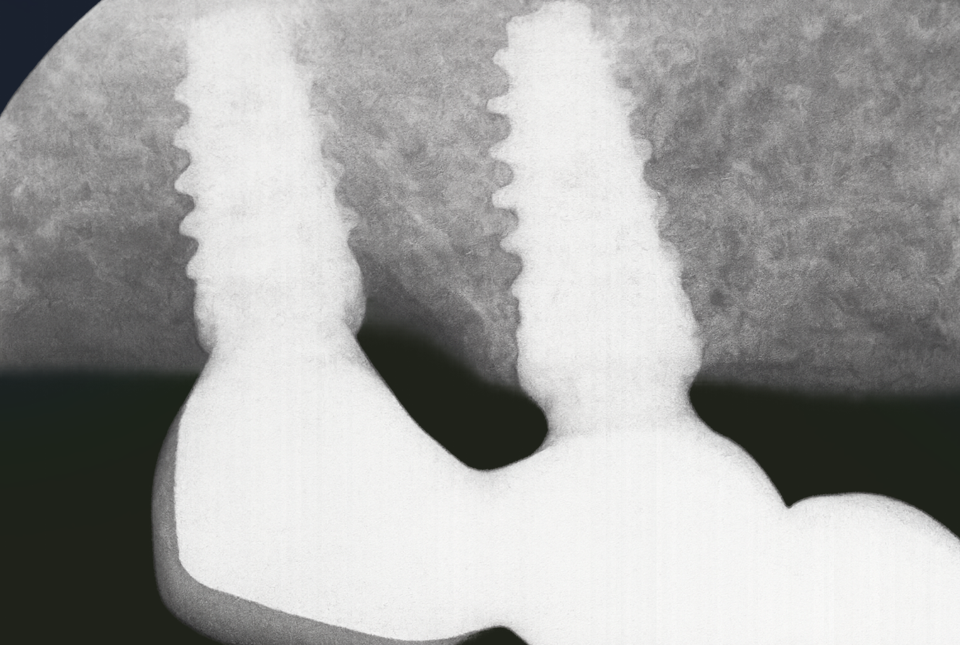

발산동 치과 예시 사진처럼 임플란트를 심은 후, 주변에 염증이 생겨나 뼈가 파괴되면 나사산이 겉으로 드러나게 됩니다.

이런 경우, 소량의 골이식과 함께 PDRN를 사용할 수 있습니다.

그럼 사진처럼 치조골이 회복되어 임플란트를 치조골이 안정적으로 감싸게 되죠.